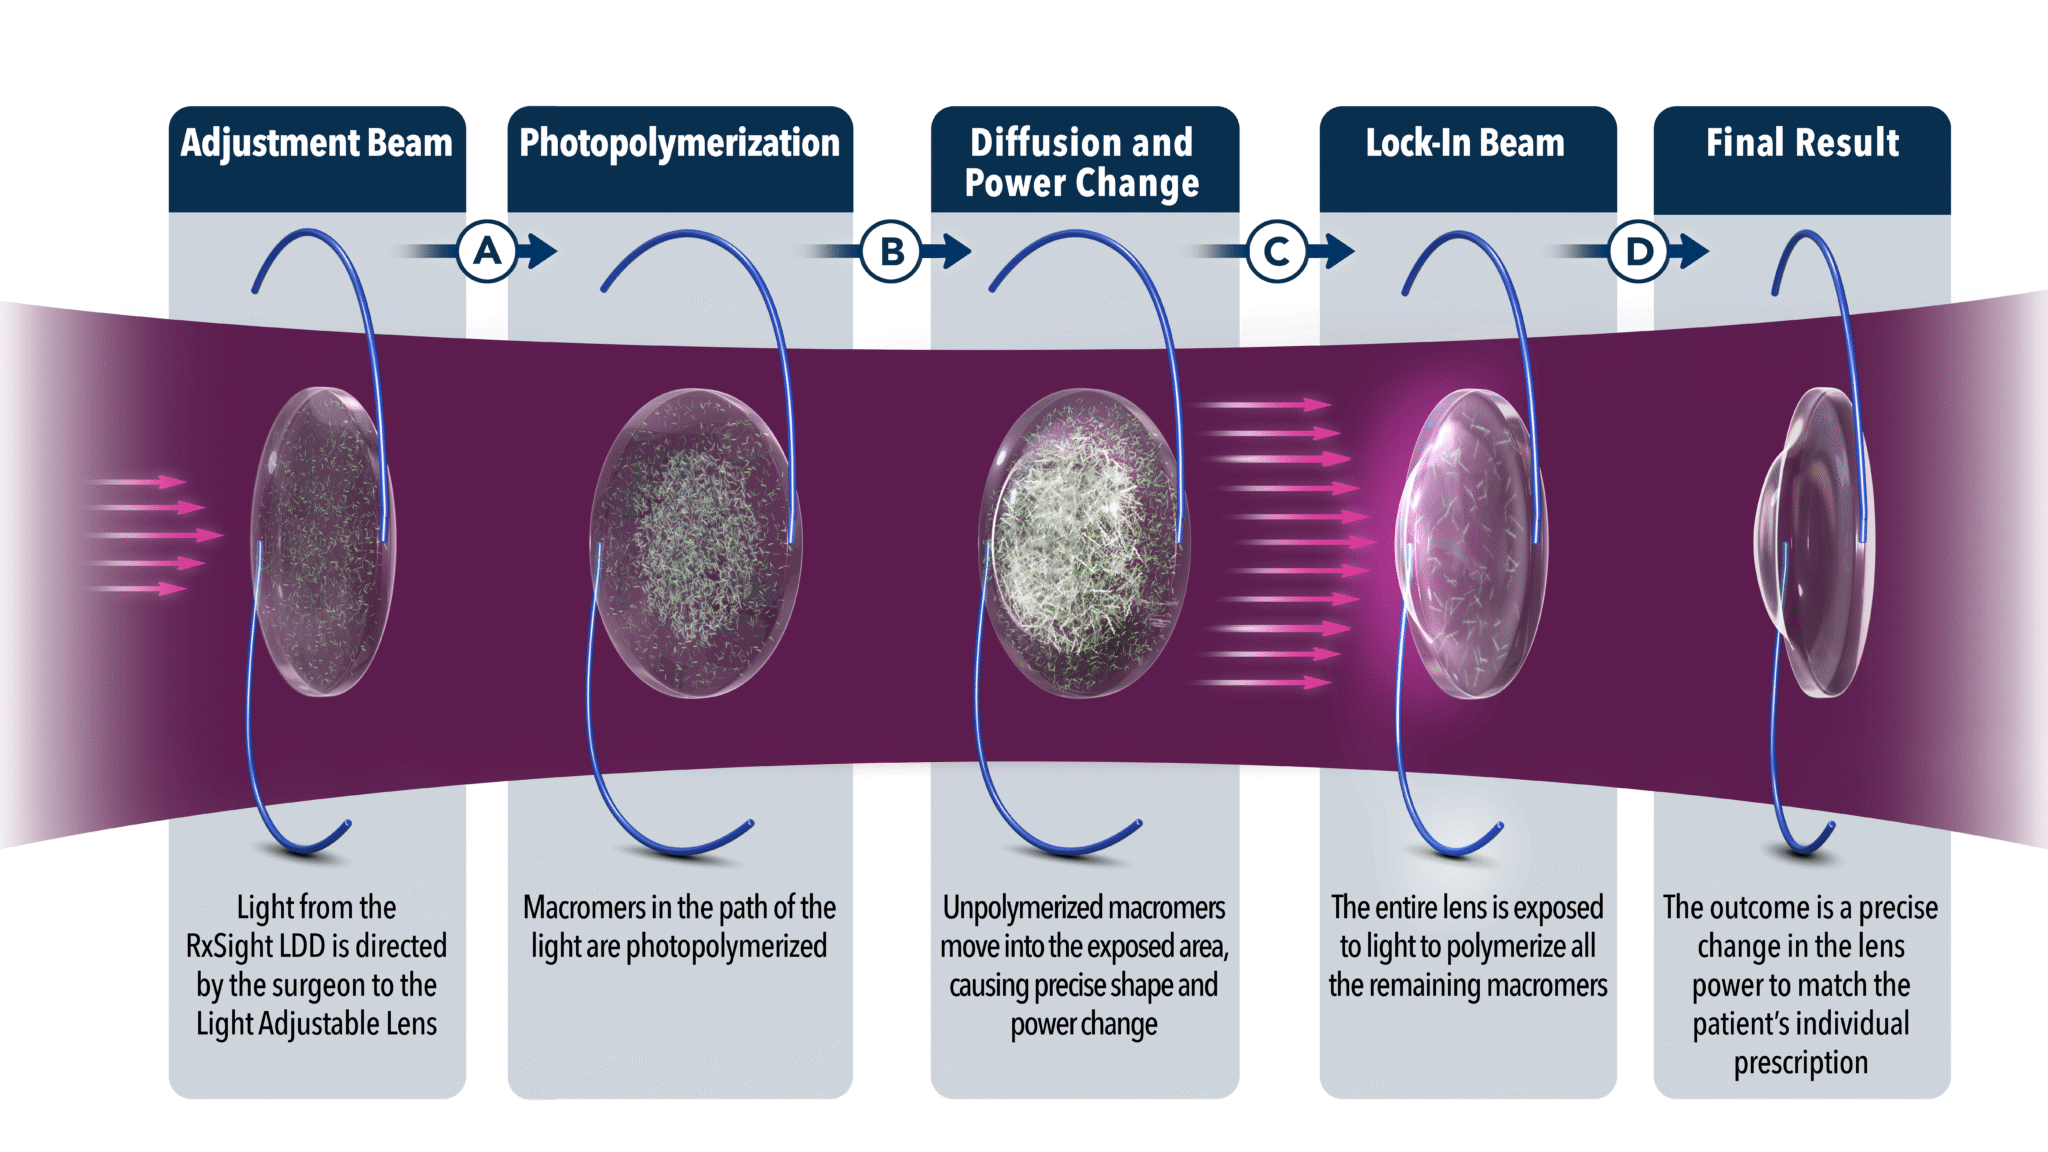

What is a Light Adjustable Lens?

The Light Adjustable Lens (LAL) is an intraocular lens placed at the time of cataract surgery that allows the surgeon to adjust the power AFTER cataract surgery is finished. Prior to this IOL’s approval, we extensively measured the patient’s eyes with multiple computers, lasers, and imaging devices to customize the IOL for each patient. We also have ORA to help make decisions during surgery and to fine tune astigmatism correction after the IOL is placed.

The Light Adjustable Lens is a completely new procedure. The LAL appears just like a typical foldable lens implant inserted through a small incision at the time of cataract surgery. The inside of the LAL is made of photosensitive monomers that, when exposed to a special light, can migrate to the periphery or center to correc residual nearsightedness, farsightedness, and astigmatism.

After the surgery is completed, the patient waits about 1-2 weeks and, once refractive stability is achieved, the lens is treated with a specially designed laser. Up to 4 different treatments can be performed to reduce refractive error as close to the desired result as possible. The treatments are painless and take 1-2 minutes per eye.

The best candidates for the LAL are previous LASIK, PRK, and RK patients, as well as patients who have previously done monovision (blended vision) or may be interested in monovision (blended vision). The way for patients to think about this IOL is that it is basically doing LASIK or PRK after cataract surgery without having to do a separate surgery. The only drawbacks are the lack of a multifocal version, the need to wear UV protecting glasses for up to a month at all times outdoors until the lens is finally “locked” into place, and the cost.